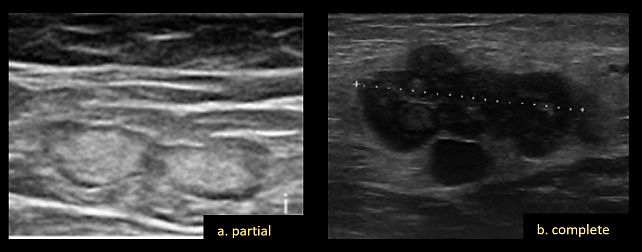

- Grouping: positioning of nodes unusually close together, further defined as 'partial', when the nodes remain distinct, or 'complete' when they fuse, such that individual boundaries become indistinguishable (Figure 10).

10

Grouping of lymph nodes, which can be partial (a) or complete (b).